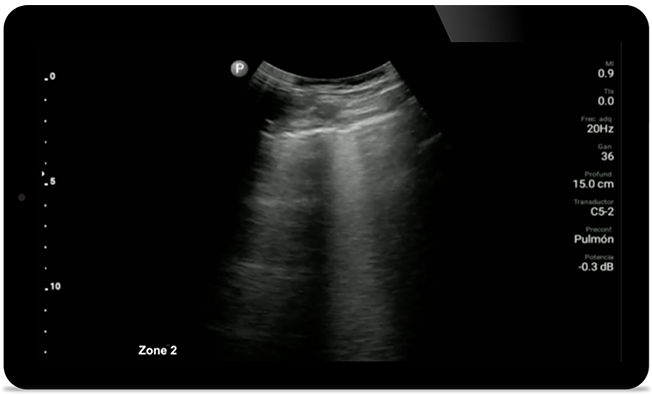

Keep an eye on COVID pneumonia

Lumify can help give results similar to a chest CT when evaluating pneumonia and adult respiratory distress syndrome.

• 12 to 4 MHz extended operating frequency range • Aperture size: 34mm • 2D, steerable color Doppler, M-mode, advanced XRES and multivariate harmonic imaging, SonoCT • High resolution imaging for shallow applications: soft tissue, vascular, superficial, musculoskeletal, and lung • Center line marker • USB-C transducer with replaceable cable